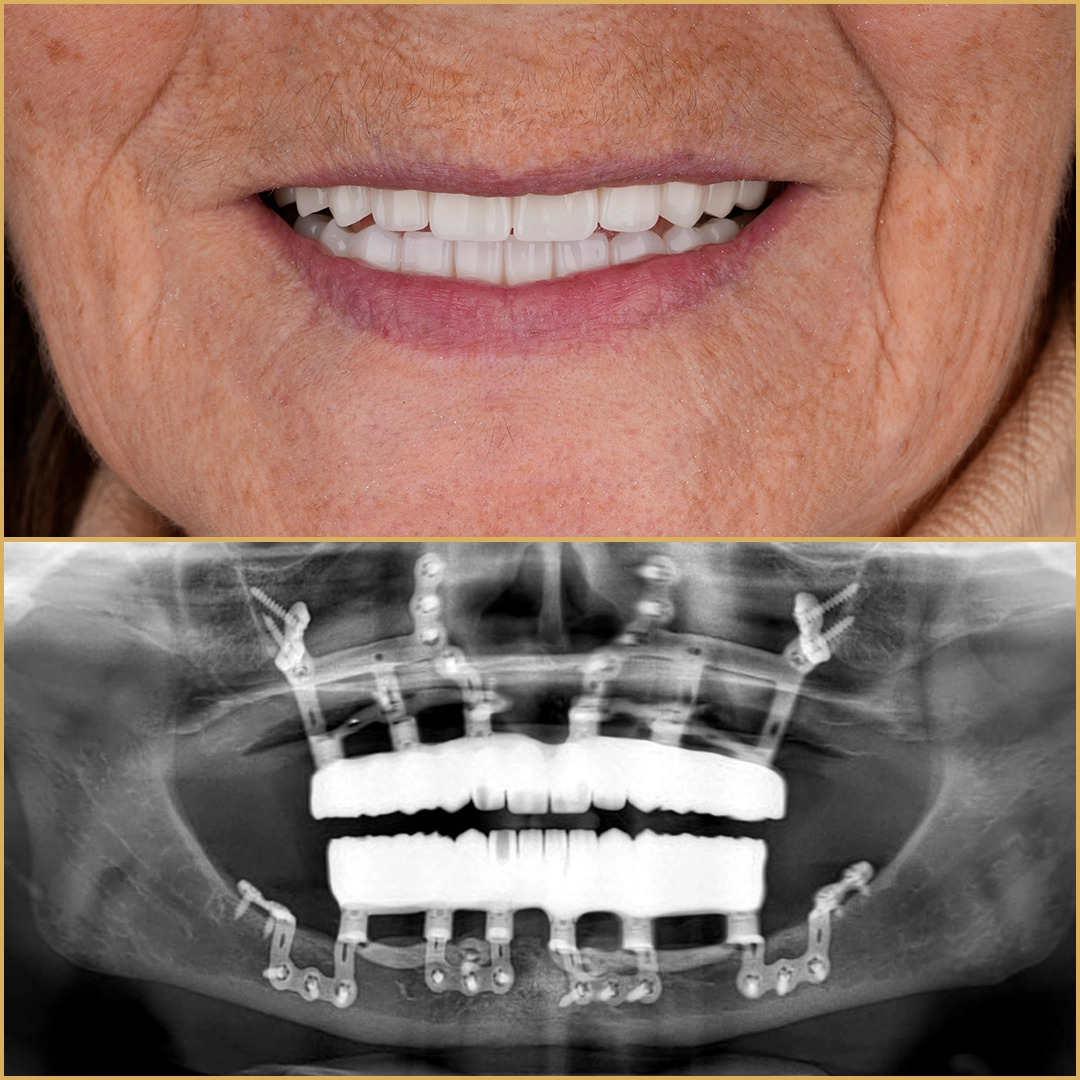

Once the solid foundation of subperiosteal implants is in place, Vitrin Clinic elevates the treatment with personalized Hollywood Smile restorations. “The beauty of our approach is that patients never have to sacrifice aesthetics for function,” Dr. Alsaman notes. “Our smile designs are meticulously crafted based on facial structure, skin tone, and personality, resulting in bright, natural-looking smiles that truly enhance each patient’s unique beauty.”

Unlike generic treatments, each Hollywood Smile at Vitrin Clinic is a bespoke creation, fabricated using premium materials that replicate the translucency and texture of natural teeth. This attention to detail consistently impresses patients and critics alike.

With a decade-long success rate exceeding 90% for subperiosteal implants combined with high-quality restorations, Vitrin Clinic’s results speak volumes. Testimonials from international patients praise the clinic’s expertise, transparent communication, and the life-changing impact of their new smiles.